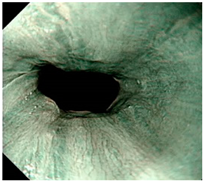

![]() | LA grade normal | LA grade normal | LA grade normal |

| Image | GERD Endoscopy Grading | Gerd-VGGNet | GerdNet-RF |

|---|---|---|---|

![]() | LA grade normal | LA grade C–D | LA grade normal |